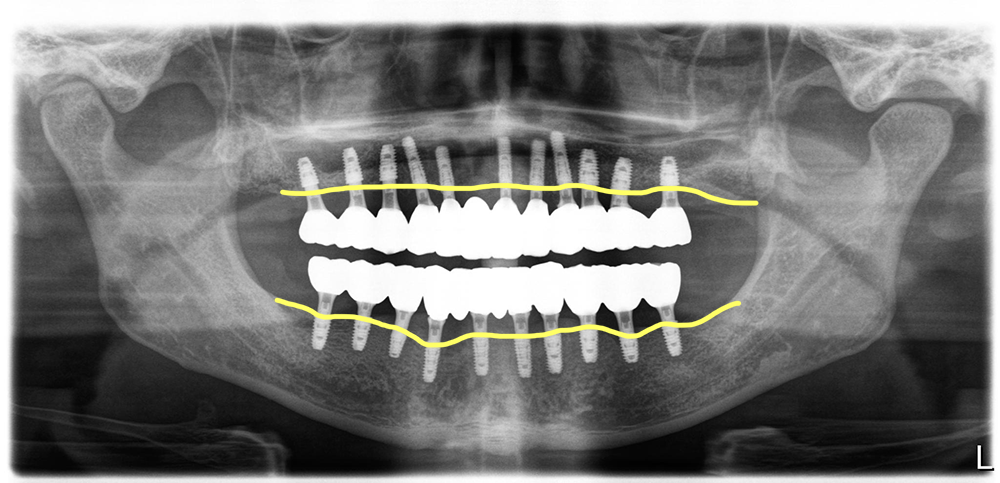

염증조직을 모두 제거후 위아래 임플란트 21개 식립(위 11개, 아래 10개)

식립한 임플란트 21개에 지대주를 연결해 수술후 바로 임시치아를 적용

수술직후에 지대주를 연결해서 스캔을 한 다음 삼차원 디자인을 하고 밀링과정을 거친후 PMMA로 임시치아를 장착하고 있는 모습입니다.

이 분은 치주염이 심했지만 다행히 임플란트 식립을 하기 위한 가용골이 적절히 있었고, 간단한 뼈이식을 일부 하는 정도로 모든 임플란트를 식립할 수 있었습니다. 그리고 임플란트의 위치도 대체적으로 적절한 위치에 식립한 가능한 상태였습니다. 뼈가 불규칙하게 파괴되는 경우에는 임플란트의 상하위치가 좋지 않게 되는 경우도 있지만 이 분의 경우에는 적절히 좋은 위치에 가능했습니다.

수술후 4개월 차에 전체적으로 스캔을 한 다음 보철디자인을 합니다.